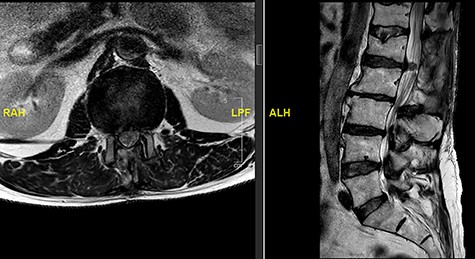

The updated MRI scan showed large disc prolapse at L4/5 level (Fig. 4) and the patient underwent emergency laminectomy/discectomy at L4/5. Post-operatively the patient’s pain improved however there still a retained loss of perineal sensation to pin-prick, a urinary catheter tug awareness was present and a good lower limb power was documented. The patient was discharged on the third post-operative day having been successfully mobilized and decatheterized with spontanous micturition.

The patient represented just over a month following the surgery to report about new onset weakness in the plantar flexion bilaterally, urinary incontinence, persistence of perineal sensation loss and new erection problems. There was no report of any pain and ambulation was still at ease. An MRI scan was organized a few days later (Fig. 5). The finding was deemed to be an IDH. Therefore, revision surgery followed the next day, with a durotomy and extraction of intradural disc fragments. As the patient had sphincter disturbance with neurogenic bladder and bowel difficulties, a referral to the regional spinal injury unit for aftercare as well as to the sexual dysfunction clinic for erection problems were organised.